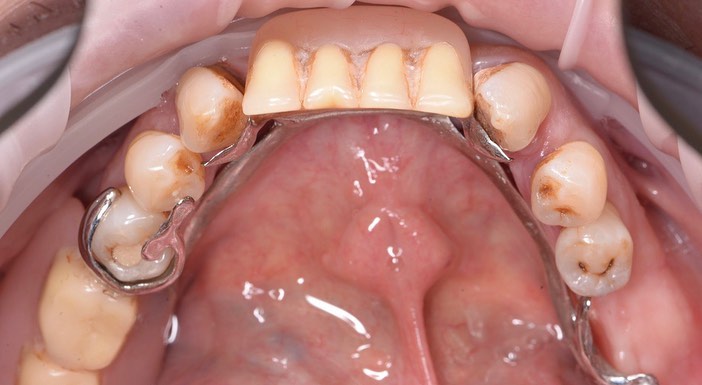

Тотальная имплантация AnyOne методом all-on- 4.

Иващенко Александр Николаевич: клинический стоматолог-хирург, практикующий имплантолог.